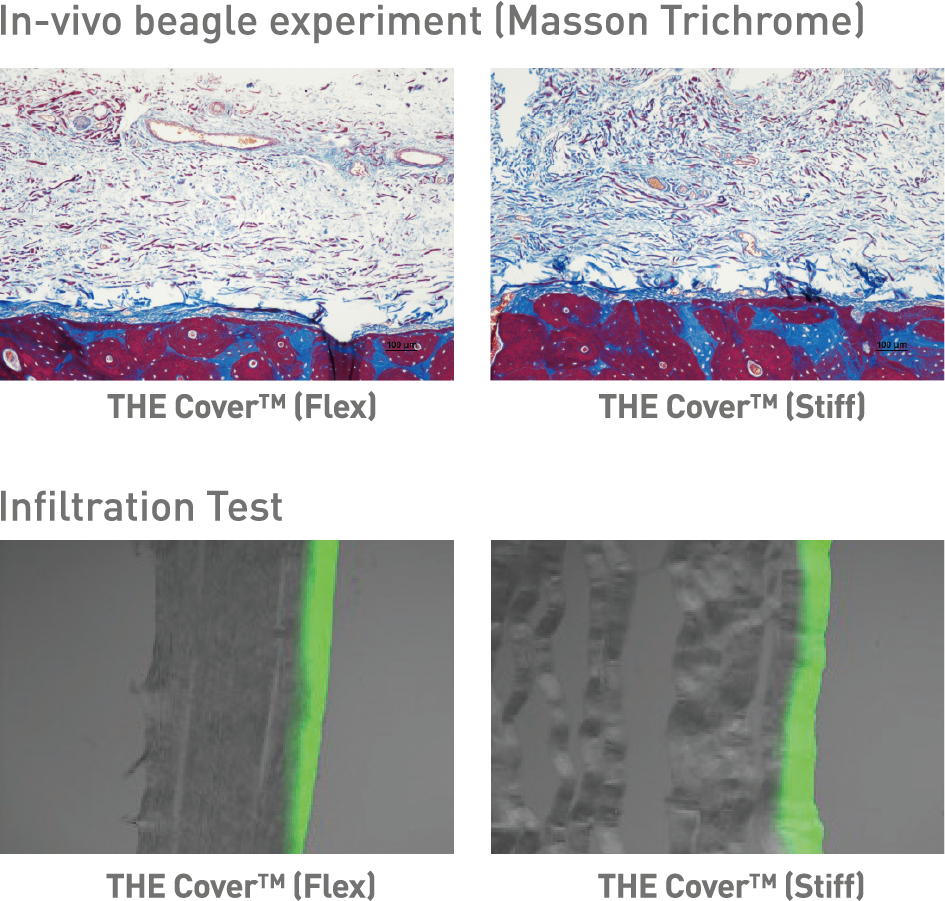

THE Cover™ is vervaardigd uit zuiver Type I collageen en kenmerkt zich door een uitstekende biocompatibiliteit en celvriendelijkheid, aangezien er geen chemische crosslinking-agenten zijn toegepast. Dit garandeert een veilige, natuurlijke integratie in het omliggende weefsel.

Er zijn twee varianten beschikbaar:

THE Cover™ Flex – voor optimale flexibiliteit en een bijzonder gebruiksvriendelijke handling.

THE Cover™ Stiff – met verhoogde stijfheid, ideaal voor betrouwbare ruimtebehoud.